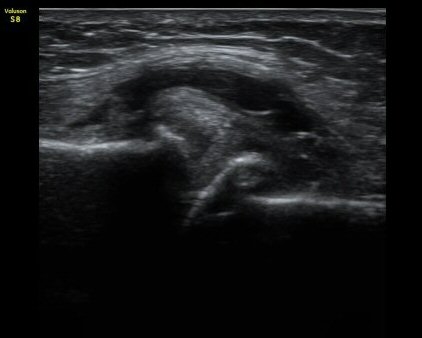

¹«¸­ µÚ ¹Ý¸·¾çÈûÁ٠Ⱦ´Ü¸é °Ë»ç¿¡¼­ ÈûÁÙÀÇ ºñÈÄ¿Í ÈûÁ٠ǥÃþ¿¡ ¼ö¾× Àú·ù°¡ °üÂûµÊ(±×¸² 4).